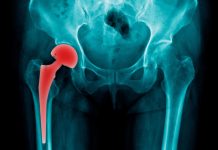

Αρθροπλαστική ισχίου. Πότε πρέπει να γίνεται αρθροπλαστική ισχίου που προσφέρει ανακούφιση από τον πόνο και βελτίωση της κινητικότητας; Πότε πρέπει να γίνεται αρθροπλαστική ισχίου Όταν οι άλλες θεραπείες (φαρμακευτική αγωγή, φυσιοθεραπείες, ελάττωση σωματικού βάρους) δεν μπορούν να καταπολεμήσουν τον πόνο του ισχίου τότε η αρθροπλαστική μπορεί να προσφέρει ανακούφιση από τον πόνο και βελτίωση της … Συνεχίστε να διαβάζετε το Αρθροπλαστική ισχίου.